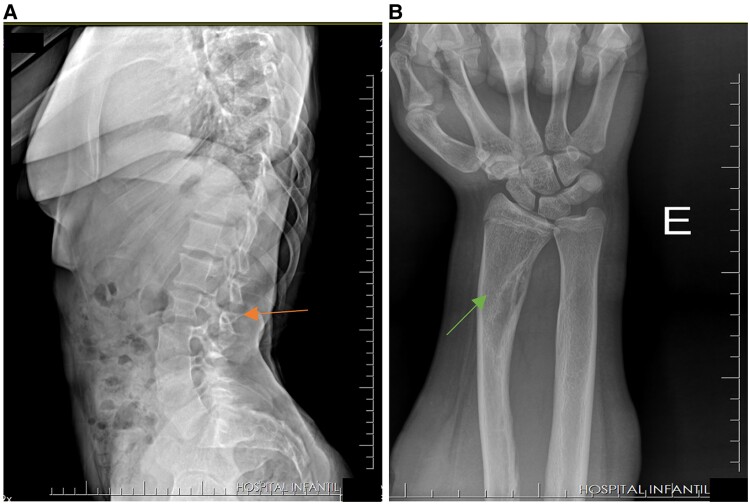

Cutaneous-skeletal hypophosphatemia syndrome (CSHS) is a rare disorder characterized by the presence of melanocytic nevi, dysplastic cortical bony lesions, and fibroblast growth factor 23 (FGF23)-mediated hypophosphatemic rickets. Herein, we describe the diagnosis of an 8-year-old girl presenting with short stature, reduced lower limb mobility, and abnormal gait due to muscle weakness and constant pain in the legs. Biochemical parameters demonstrated hypophosphatemia, hyperphosphaturia, slight increase in parathyroid hormone (PTH), high levels of alkaline phosphatase, and elevated FGF23. Burosumab improved phosphate-wasting, serum phosphorus, alkaline phosphatase, and PTH, followed by a significant mineralization in vertebral bodies evidenced by radiographic assessment. Our report shows a long-term follow-up of CSHS with a notable improvement promoted by an anti-FGF23 therapy.